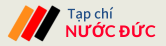

Kết quả chụp CT-Scanner ổ bụng cho thấy hình ảnh giãn đài bể thận niệu quản phải do sỏi niệu quản 1/3 giữa, sỏi thận hai bên, sỏi túi mật, thoát vị bẹn phải. Đặc biệt hơn, các bác sĩ còn phát hiện ấu trùng sán rải rác khắp cơ thể, đường kính 3-5mm.

Hình ảnh sán ký sinh khắp cơ thể bệnh nhân (Ảnh: BVCC).